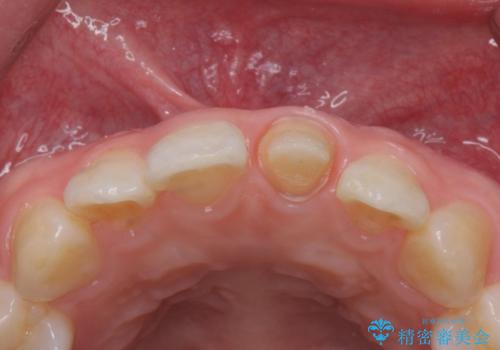

前歯の変色とガタつき ジルコニアクラウンでの修復

- 前歯の変色とガタつきが気になるとのことで来院された患者様です。

根管治療からやり直しを行った後、ジルコニアクラウンで修復することで、ガタつきと変色の両方を改善していきます。

- 左上1/再根管治療66,000円+ファイバーコア22,000円+仮歯11,000円+ジルコニアクラウン(スタンダード):121,000円 合計209,000円(税込)費用は治療当時の料金となります